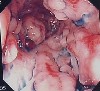

2004年08月02日 大腸ファイバー検査